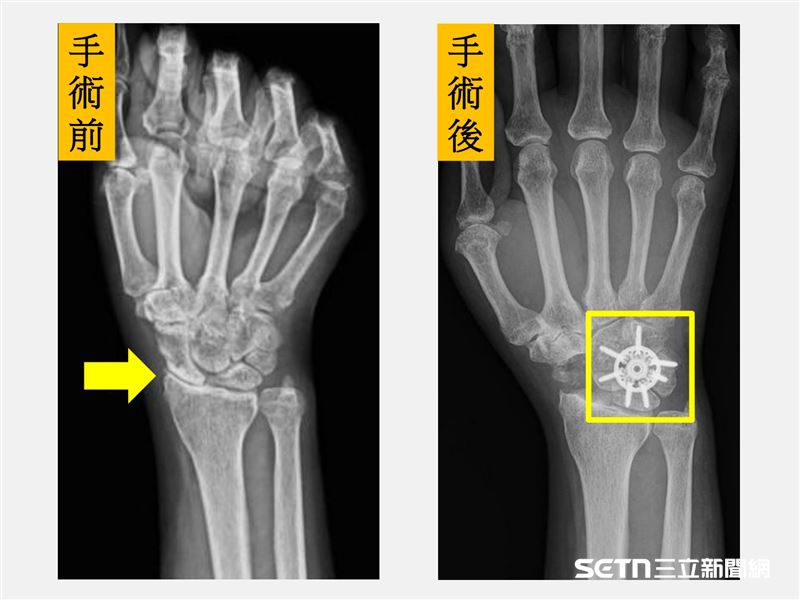

針對手術,陳重宇醫師表示,傳統的融合術多以鋼釘或螺釘固定,依最新研究顯示,環狀鋼板能提供更佳的初期穩定性,提高骨頭癒合成功率,並讓病人更早開始復健,降低僵硬與肌力流失的風險。至於劉先生的狀況,因為其症狀是手腕腫脹、活動受限和握力明顯下降,X光檢查顯示已進展至中後期病程,所以經醫療團隊討論後,劉先生接受「舟狀骨切除合併四角融合術(scaphoid excision and four corner fusion)」,並使用新型環狀鋼板固定,復原順利。